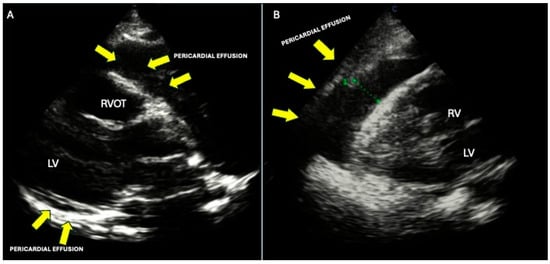

9. Pericardial Involvement

- Mori, S.; Bertamino, M.; Guerisoli, L.; Stratoti, S.; Canale, C.; Spallarossa, P.; Porto, I.; Ameri, P. Pericardial effusion in oncological patients: Current knowledge and principles of management. Cardio-Oncology 2024, 10, 8. (In English) [Google Scholar] [CrossRef] [PubMed]

- Adler, Y.; Charron, P.; Imazio, M.; Badano, L.; Barón-Esquivias, G.; Bogaert, J.; Brucato, A.; Gueret, P.; Klingel, K.; Lionis, C.; et al. 2015 ESC Guidelines for the diagnosis and management of pericardial diseases. Eur. Heart J. 2015, 36, 2921–2964. (In English) [Google Scholar] [CrossRef] [PubMed]